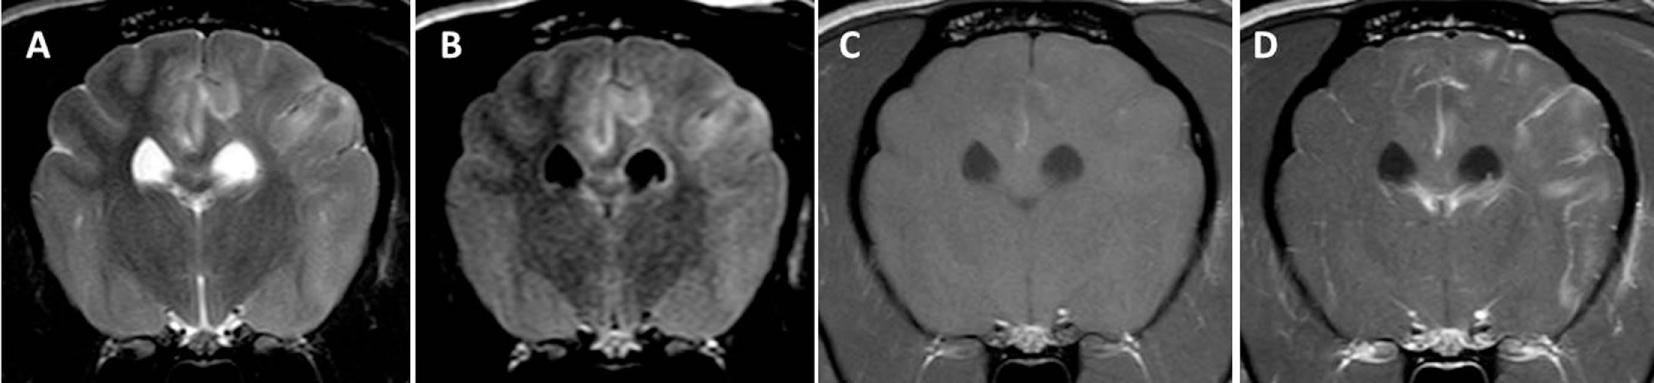

Figure 1. Transverse magnetic resonance images (3 T) of a Yorkshire Terrier (2 years, female) with necrotizing leukoencephalitis. T2 (A) and fluid-attenuated inversion recovery (B) hyperintense finger-like lesions affecting the subcortical white matter, the corona radiata, and the diencephalon. Right-sided ventricular enlargement, focal widening of sulci, and mild midline shift to the right are most likely secondary to white matter loss in the right prosencephalon. Contrast enhancing lesions as on the left side [(C) T1-weighted native; (D) T1 weighted after contrast injection] and non-contrast enhancing lesions (right side) may coexist in one patient, which most likely reflects different stages of the disease. Enhancement may be patchy or it may be seen around necrotic areas (ring-like, arrow head). Meningeal contrast enhancement is deficient.